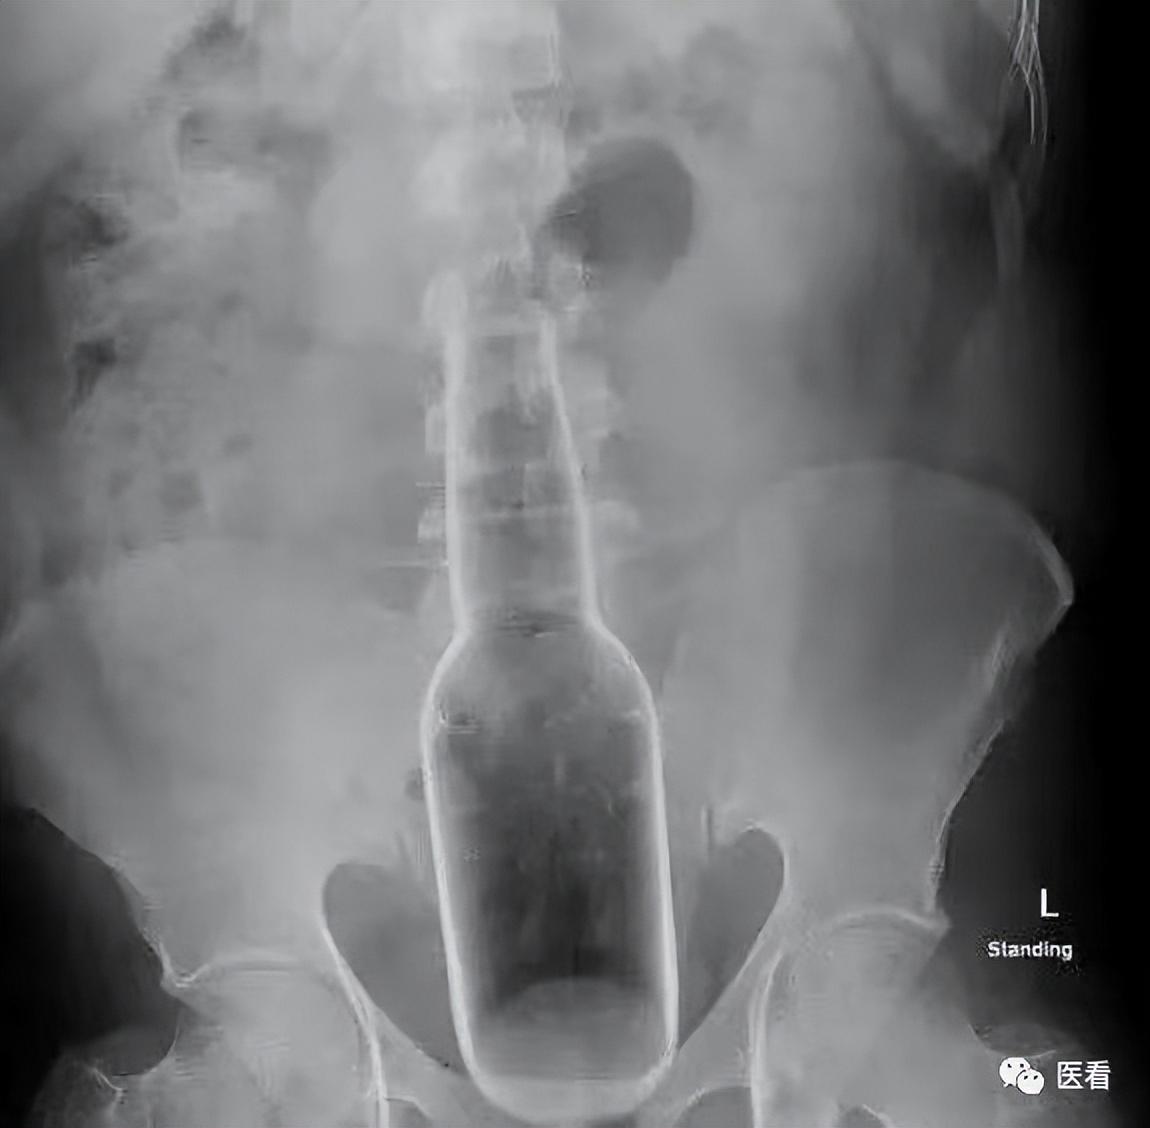

比如东苑市某男子因为“屁股痒”,所以选择用“花露水瓶”挠肛门。

没错!就是家里备用的玻璃瓶的那种“花露水瓶”。

他用花露水瓶给肛门挠痒的时候,因为一时疏忽,不小心将瓶子推入了直肠内,取不出来了。

(图片:花露水瓶位置示意图)

万幸的是,瓶子不算太长(约18cm)、肠子没有捅破、花露水有瓶盖。所以该患者比楼上塞茄子的老哥情况好的太多。